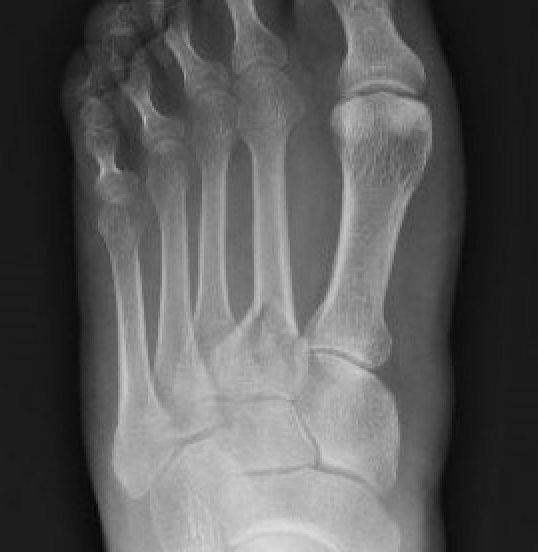

X-ray

May be negative for first 2 - 4 weeks

Subtle transverse / oblique fracture

- usually midshaft or distal

- usually incomplete

May see callous